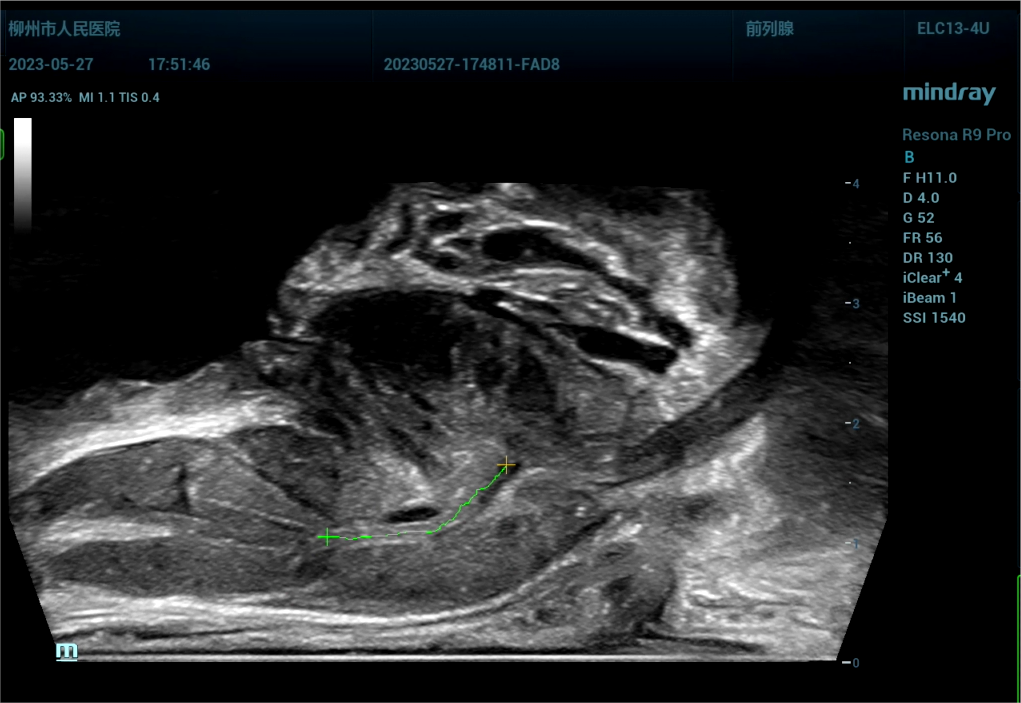

病史为,30岁年轻男性,主诉为反复尿痛2年余。临床诊断是尿路感染。

443081 截取视频 截取视频 截取视[00_01_11][20230614-074802].png